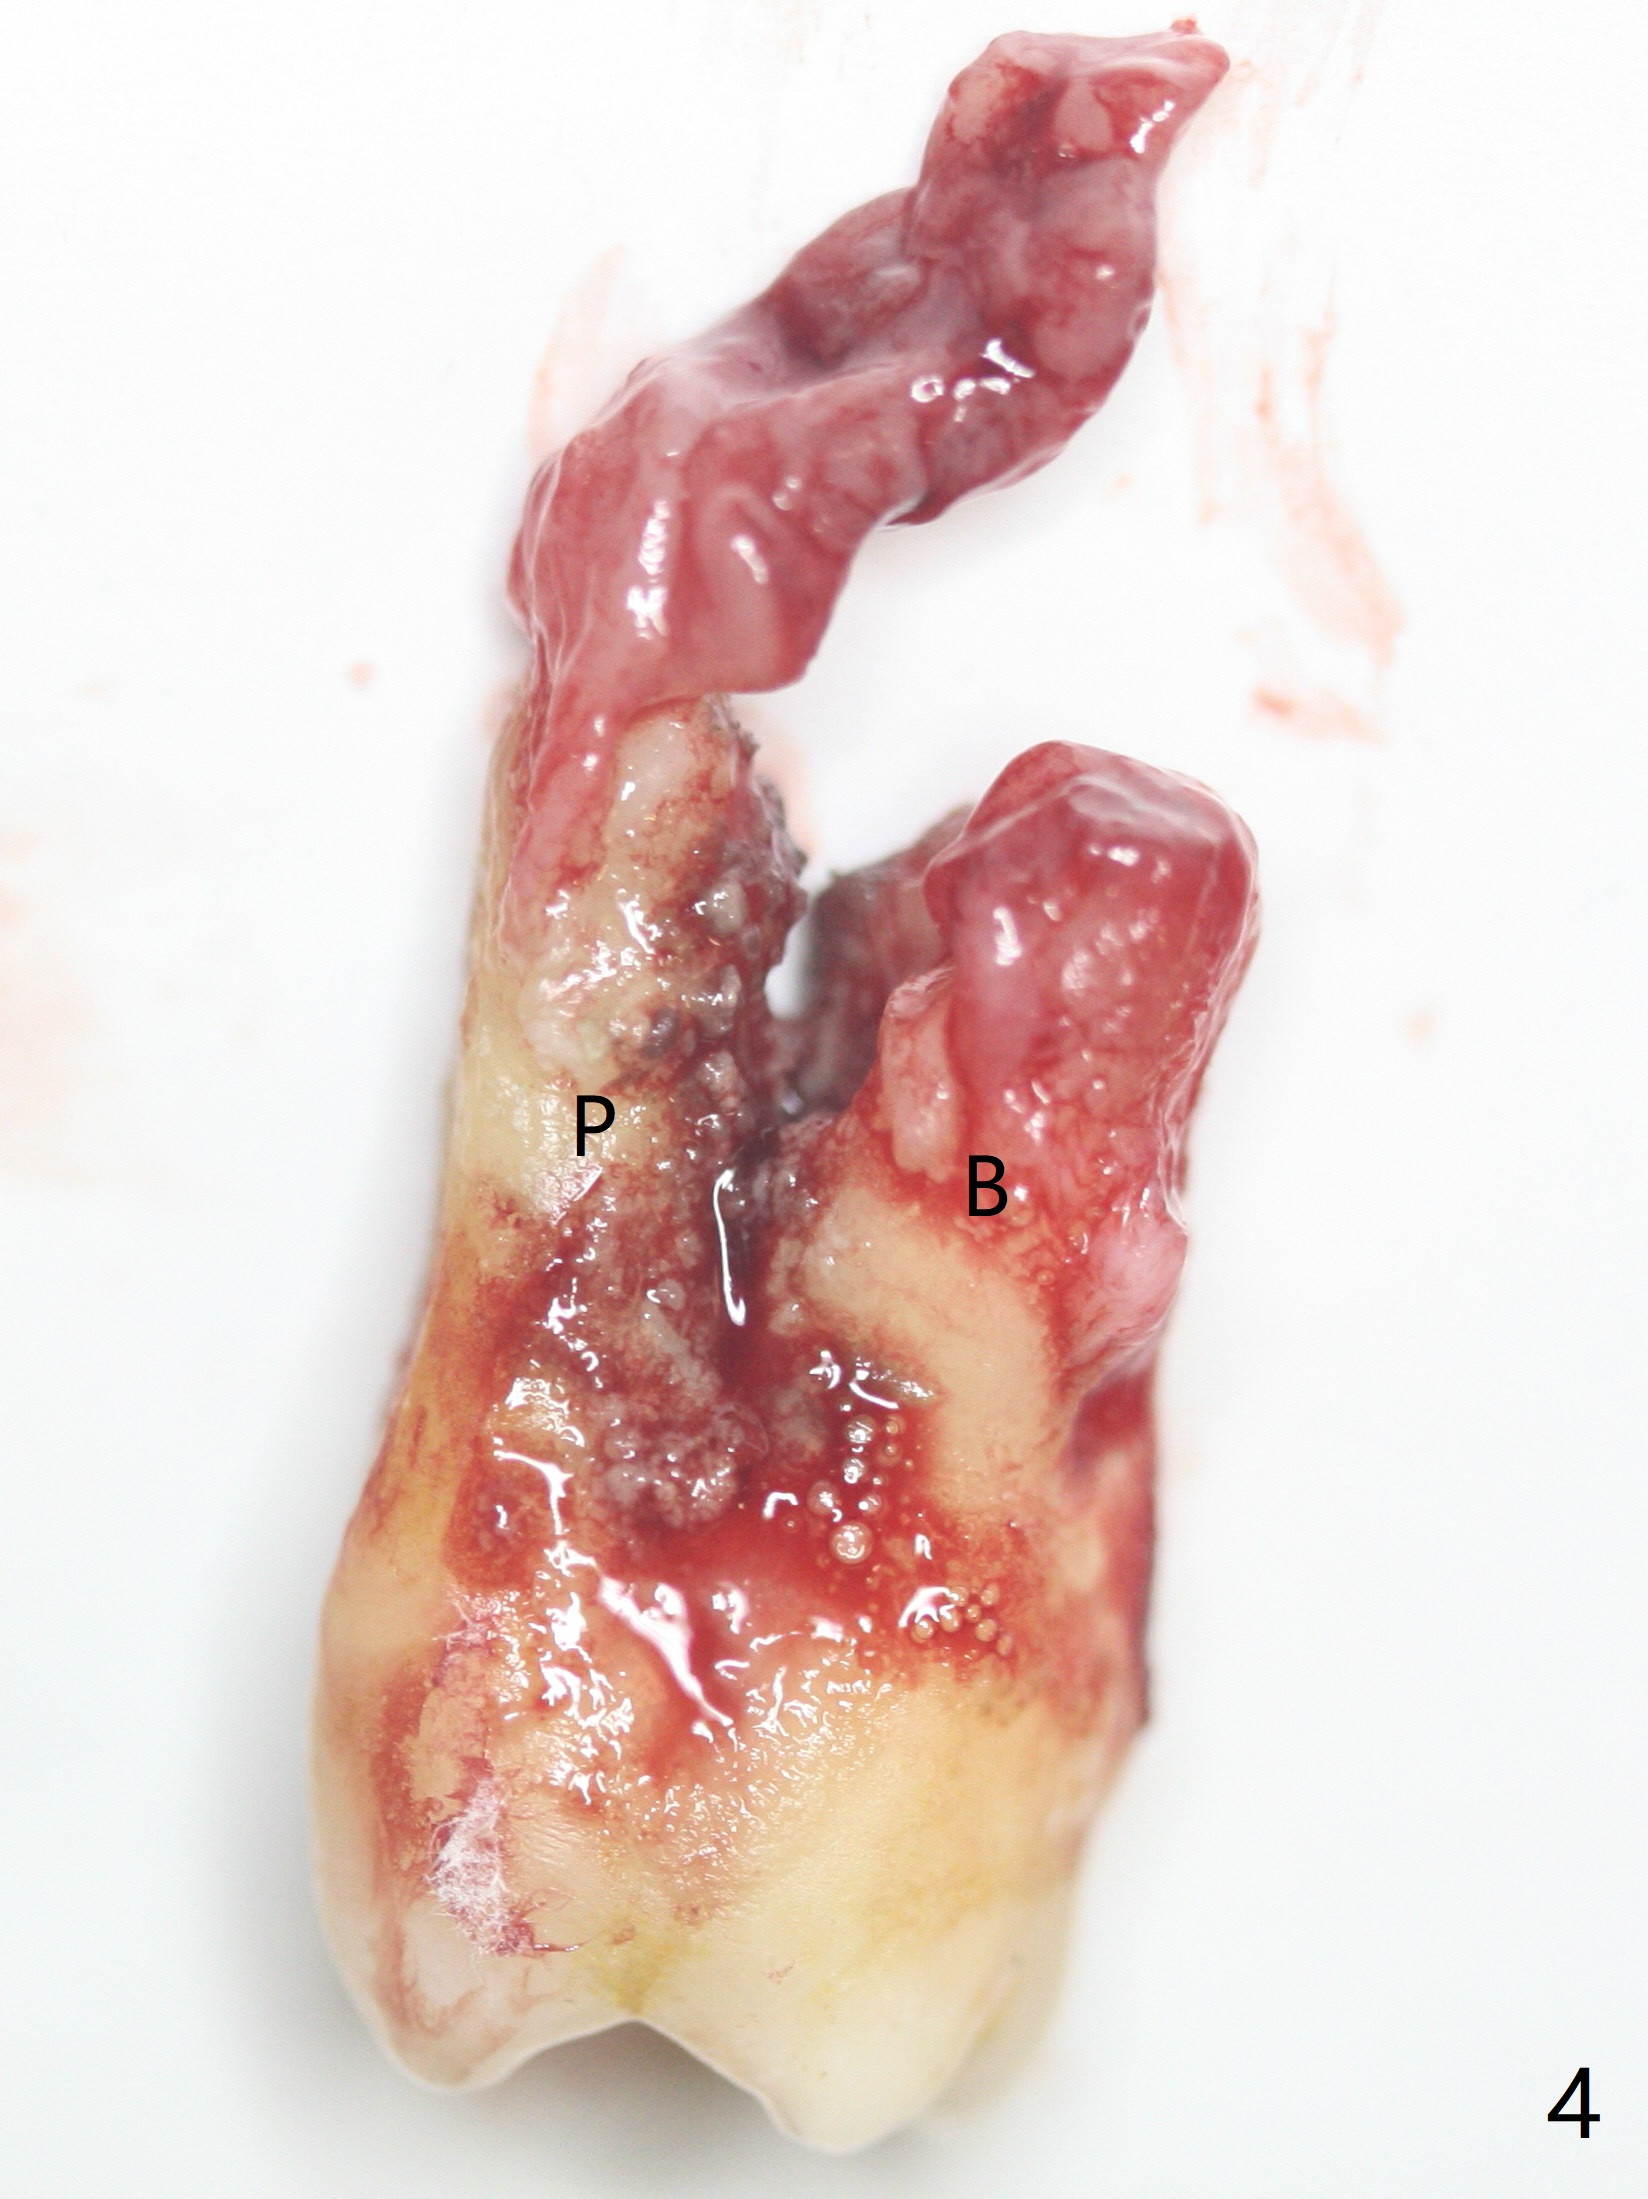

A 62-year-old man does not masticate on the right side due to facial paralysis (Fig.1 (pan taken ~ 8.5 years earlier)). Two years 9 months post #31 extraction, the tooth #2 has supraerupted (Fig.2). Nearly 7 years post extraction of #31 (Fig.3), the patient requests extraction of the supraerupted tooth because of repeated infection (Fig.4 distal view of the extracted tooth). There is calculus in the furca between the palatal (P) and buccal (B) roots. To facilitate bone regeneration in the distal surface of the tooth #3, Osteogen plug is placed in the distal portion of the socket of #2 (Fig.5 O), while allograft in the mesial one (*).